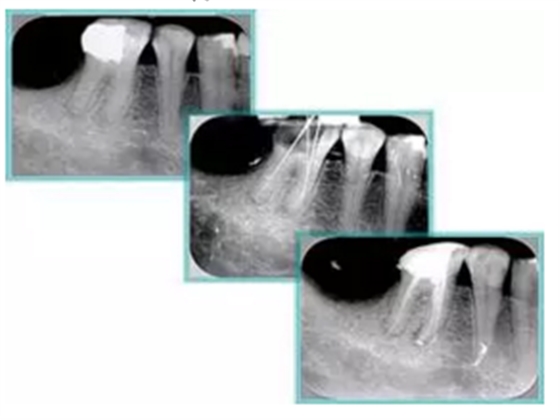

7. 器械折斷

右圖及下圖為器械折斷的 X 線片。箭頭處示折斷器械。

解決方法:

( 1 )取出。

( 2 )通過。

( 3 )重新確定工作長度,充填。

( 4 )根尖手術(shù)。

器械折斷可以不用取出,取出的原因多是患者心理因素。留在里面的器械關(guān)鍵是進(jìn)行消毒,預(yù)防性使用抗感染藥物,預(yù)防感染。